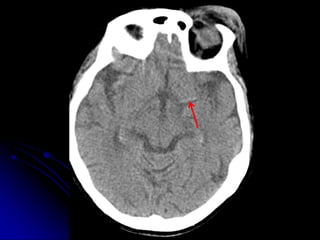

• HEAD/CSPINE

• Non contrast

• 1mm acquisition, displayed thicker

• Coronal, sagittal reformats

NON-CONTRAST

C-SPINE IMAGING

ALGORITHM

• CT

• MRI (depending upon Hx, PE, CT

findings)